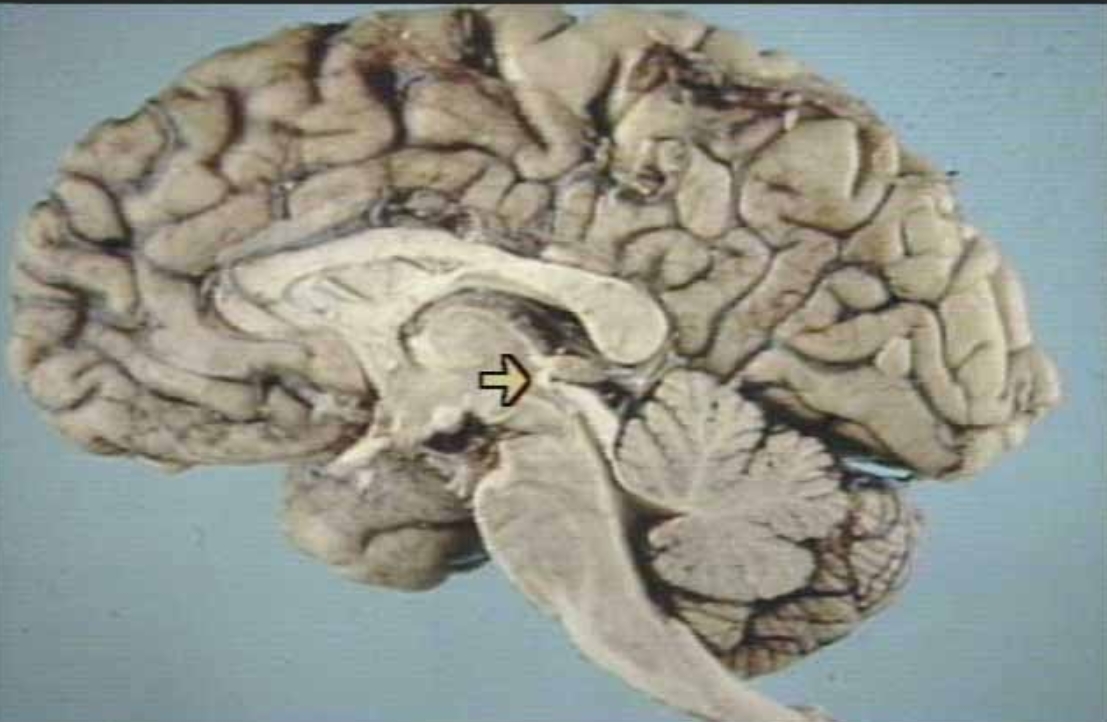

What is the arrow pointing at?

Posterior Commissure (arrow)